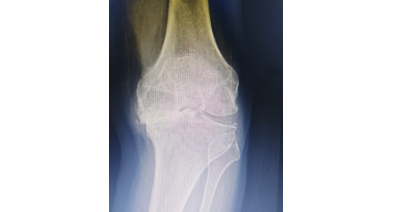

“骨质增生”or“长骨刺”大揭秘

膝盖骨质增生